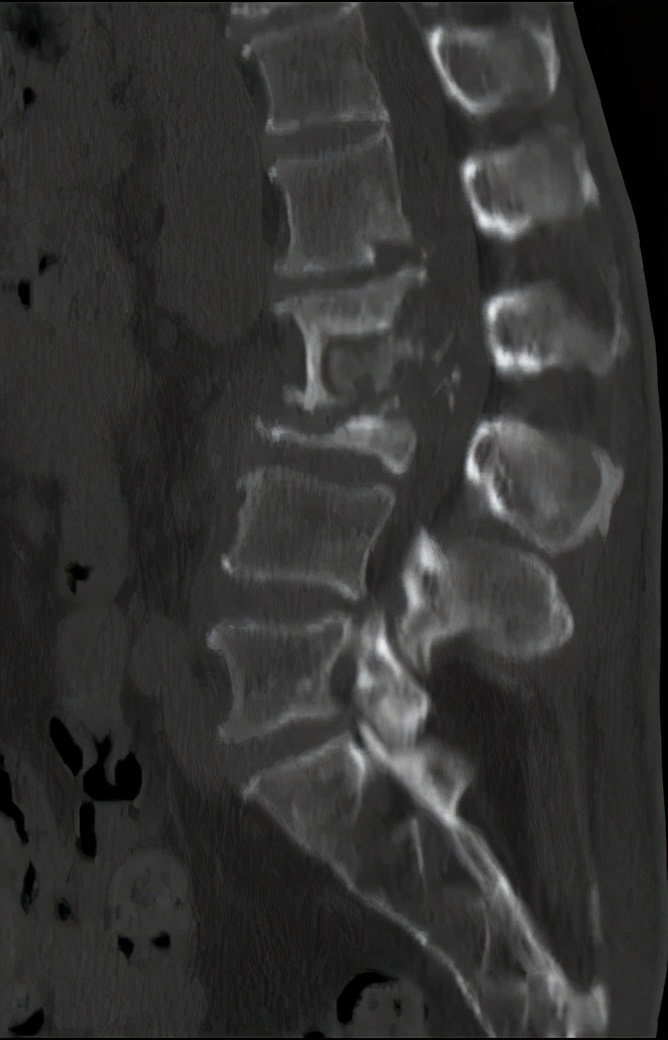

典型的腰椎结核CT影像是:骨质破坏,椎间隙消失, 死骨形成,塌陷,后凸畸形形成。

患者腰背部有骨性后凸,出现成角畸形

5、影像检查。腰椎间盘突出症影像检查 CT及核磁共振检查可见间盘突出纤维环,腰椎结核影像检查DR可见椎间隙变窄,CT及核磁可发现骨质破坏。